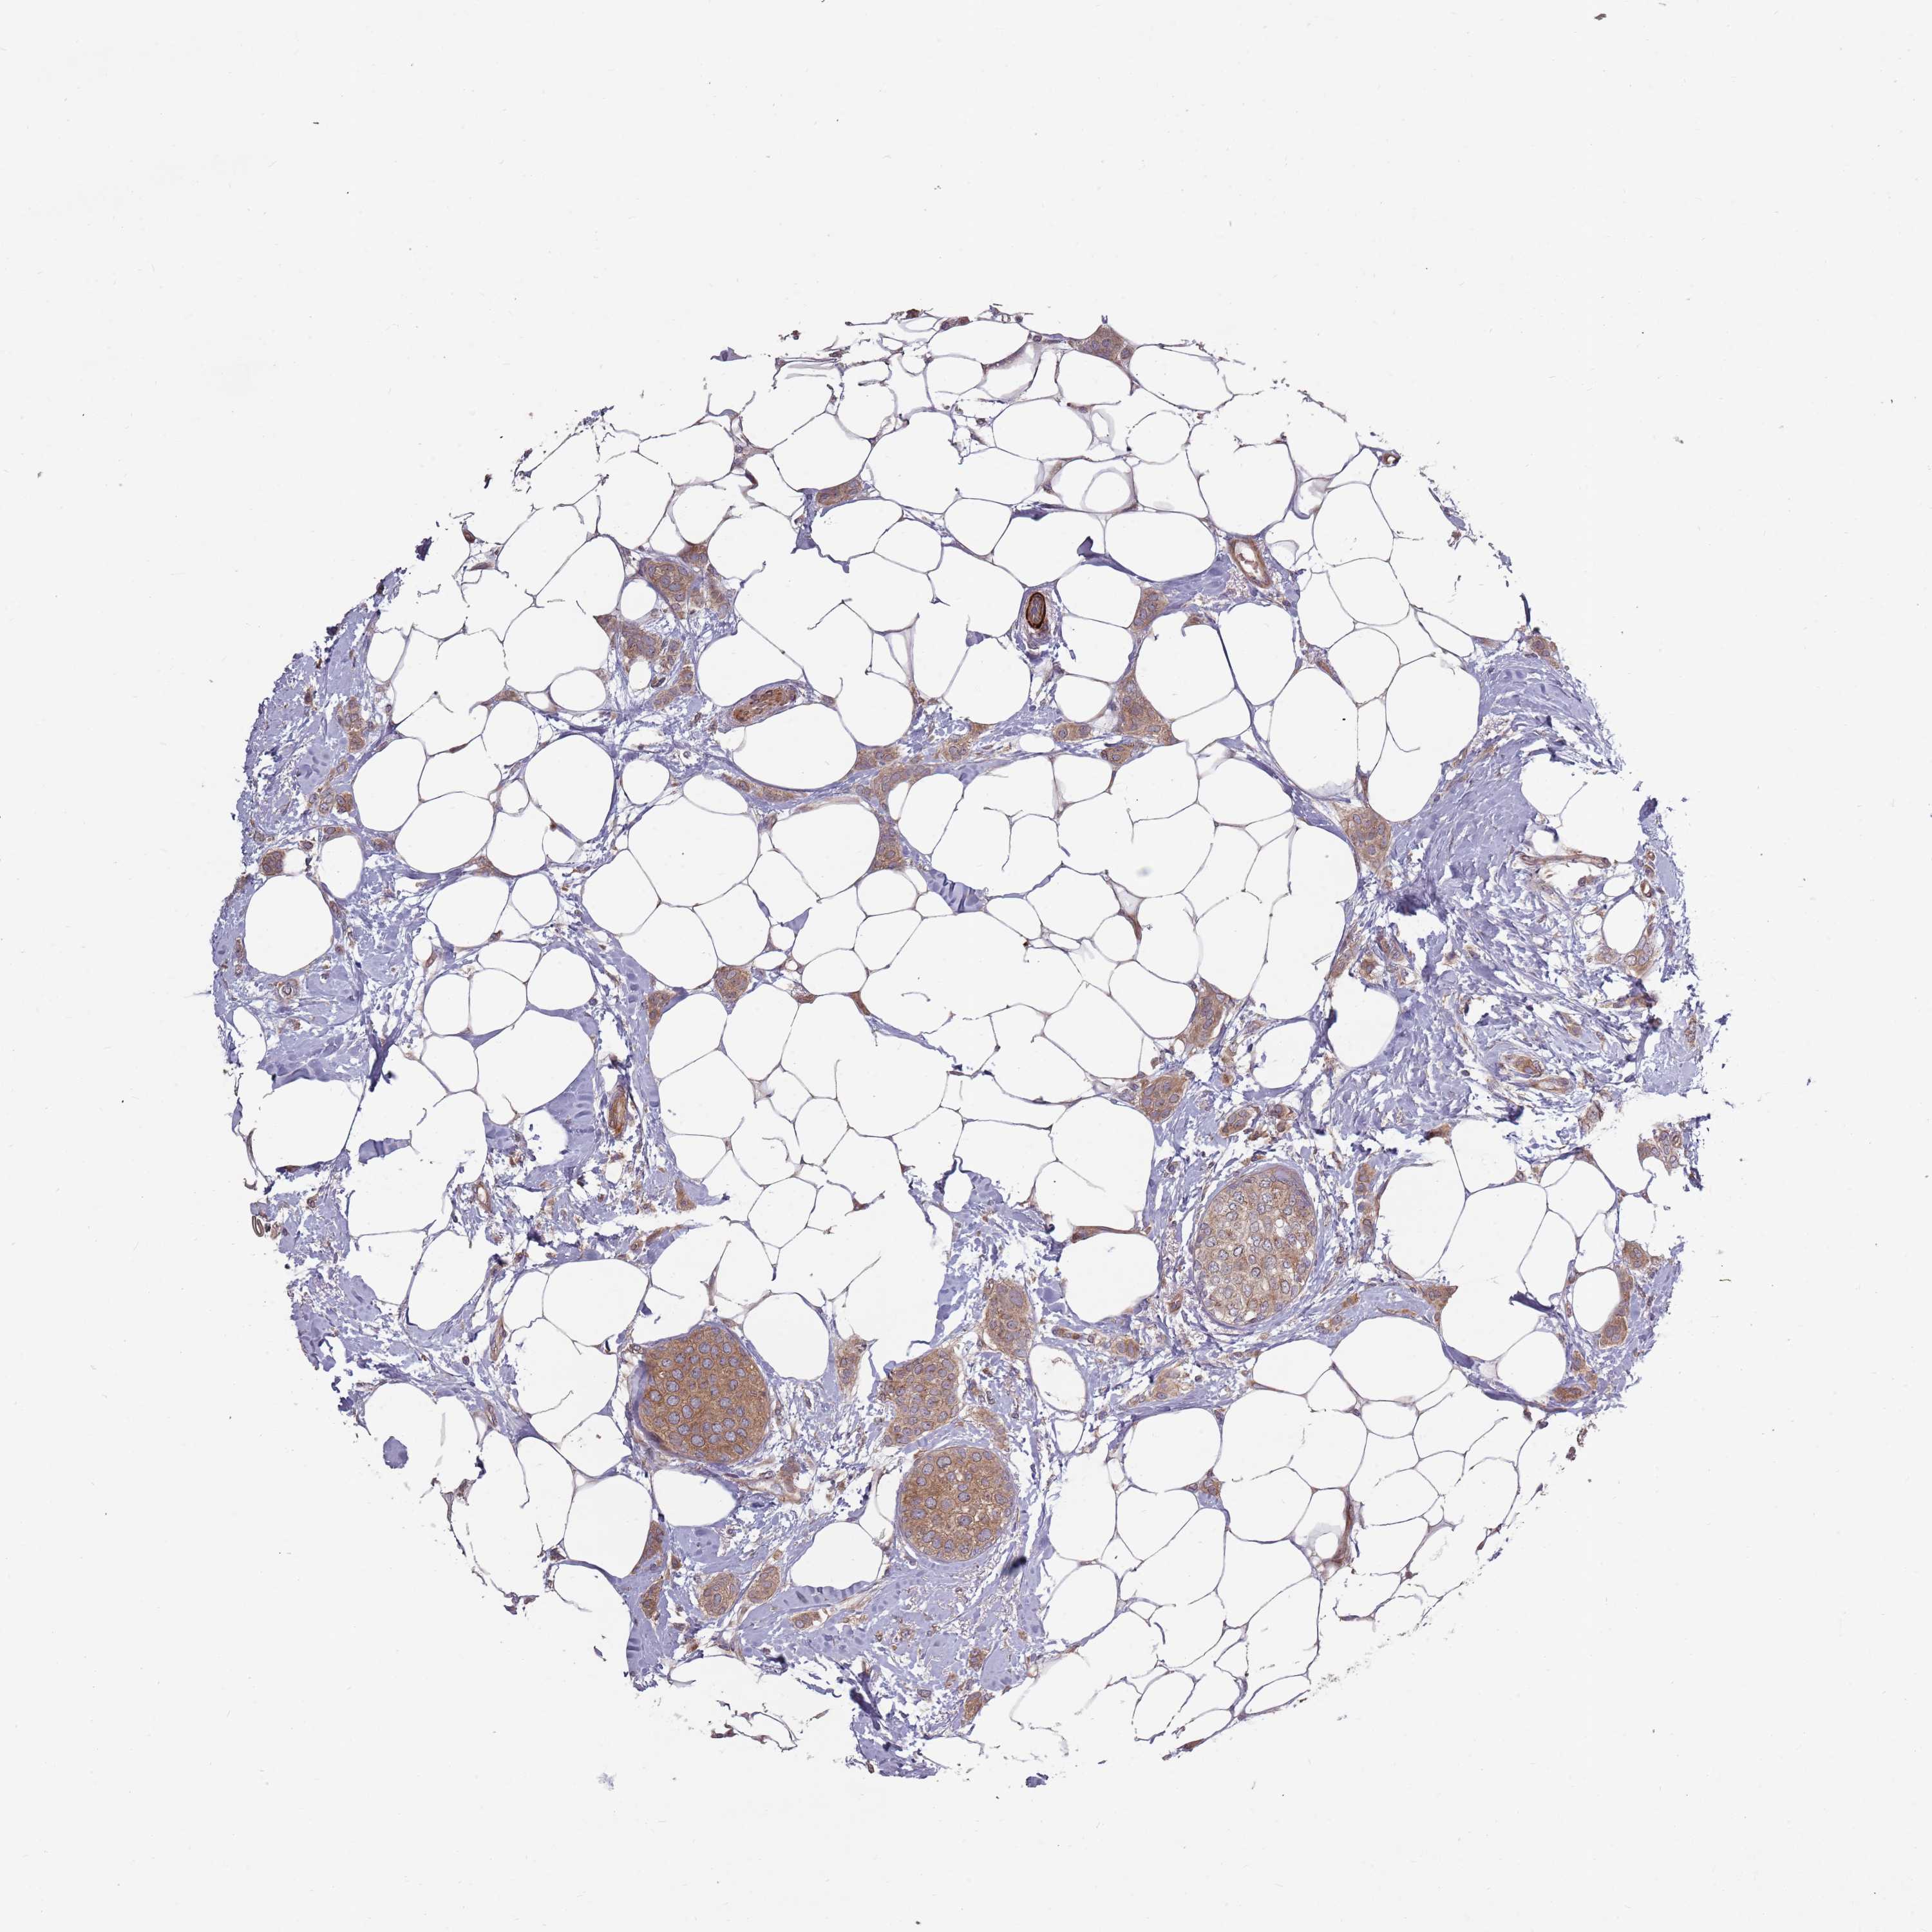

CANCER BREAST CANCER Show tissue menu

BRCA TCGA BRCA VALIDATION PROTEIN EXPRESSION